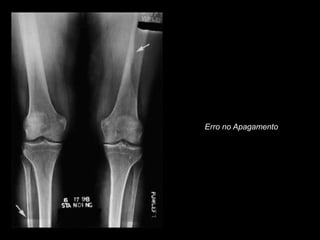

Erro no Apagamento